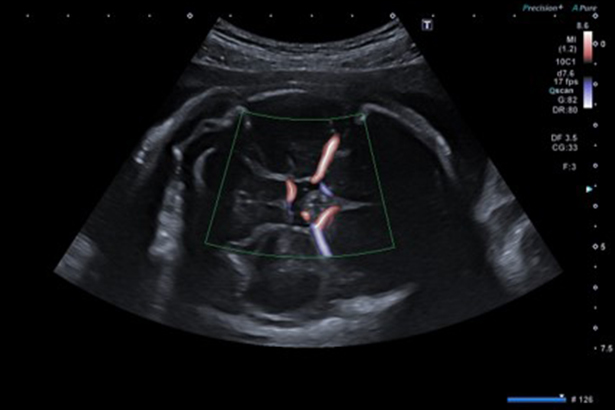

以3D形式更直觀地顯示彩色多普勒,顯示清晰并富有細節。即使是纖細的血管,Doppler Luminance 都可以高幀頻地顯示并保持整體二維圖像質量。